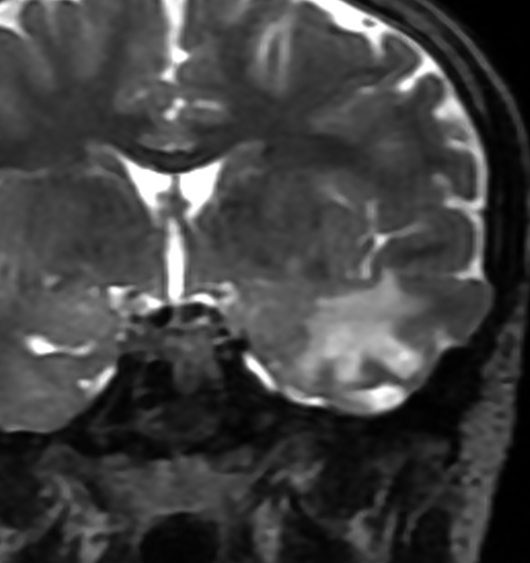

成人の頭頂葉の例

無症状で偶然発見されたものです。CTで石灰化があり,部分的にガドリニウム増強されます。乏突起膠腫グレード2との鑑別が難しい例です。乏突起膠腫より放射線化学療法に治療抵抗性ですから,もちろん治療選択は全摘出です。